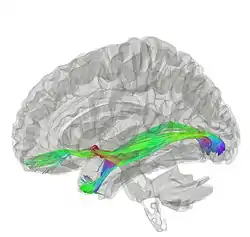

Tractography of anterior commissure | |